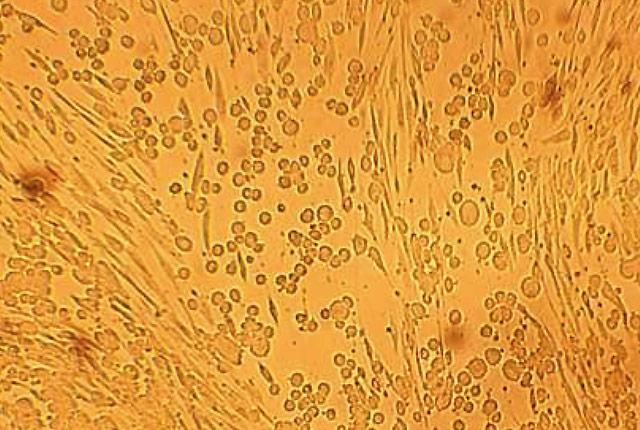

The line between the human herpes simplex viruses - HSV-1 and HSV-2 - is blurrier than previously thought, according to a new study published this week in the Journal of Infectious Diseases .

Researchers found that HSV-1 and HSV-2 are mixing together to result in several new, different recombinant versions of herpes.

HSV-1 and HSV-2 are two of the most common viruses affecting people. Moreover, humans are the only mammals that have two types of herpes simplex viruses.

Both viruses look alike clinically and are sensitive to the same drug, acyclovir. But they are genetically different. HSV-1 most commonly affects the mouth, while HSV-2 usually causes genital lesions.